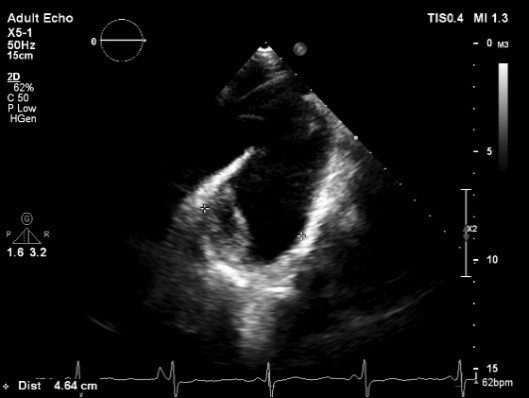

马凡综合征患者最先表现的是主动脉根部的扩张。马凡患者早期表现为主动脉窦明显扩大,呈“蒜头样”或“梨”形,在超声上主要表现为单独的窦部增宽(正常成人<3.5cm)(图1),或者整个根部(瓣环、窦部、窦管交界)增宽甚至扩张(图2),有时在超声图像上可见窦管交界消失并伴随着升主动脉的扩张。正常患者当根部>5.5cm 时就建议手术治疗,而马凡综合征的患者则在根部>5.0cm时建议手术治疗。

图1、主动脉窦部增宽>3.5cm